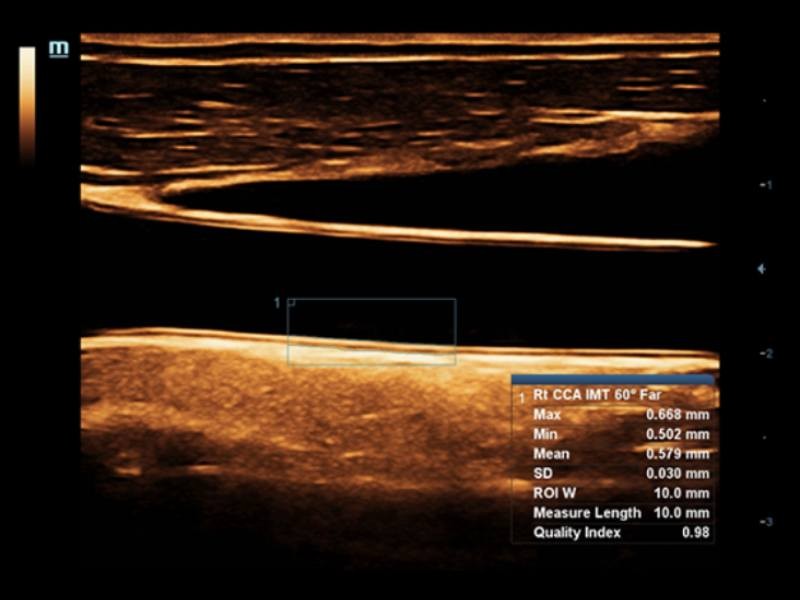

Transdutores ComboWave

Comparados aos transdutores tradicionais, os transdutores ComboWave utilizam um novo tipo de material piezoelétrico composto a fim de otimizar drasticamente o espectro acústico e reduzir a impedância acústica. Melhor integrados à exclusiva tecnologia 3T da Mindray, os transdutores lineares ComboWave permitem desfrutar de um desempenho excepcional proporcionado por incríveis resoluções e consistência das imagens em tireoide, mama, vascular e mais.